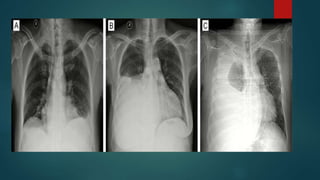

CXR  Lateral decubitus*CXR requires at least 75 ml of fluid  CXR PAV requires at least 150 ml of fluid to be detected  Supine CXR are fallacious to detect pleural effusion  CXR PA view d/ds Subpulmonic effusion Costophrenic and cardiophrenic recesses Blunting of hemidiaphragm Homogenous fluid dense radio-opacity in the lung field and making meniscsus without any bronchovascular markings within Large effusions causes underlying lung collapse and mediastenal shift to opposite side

Exceptionally on CXR Loculated pelural effusion and effsuions in fissures are non dependent  Parapneumonic effusions are difficult to be detected on CXR Grading of effusion on CXR  Mild - Up to causing CoP angle blunting  Moderate - In between  Massive - almost entire hemithorax opaque with collapsed lung